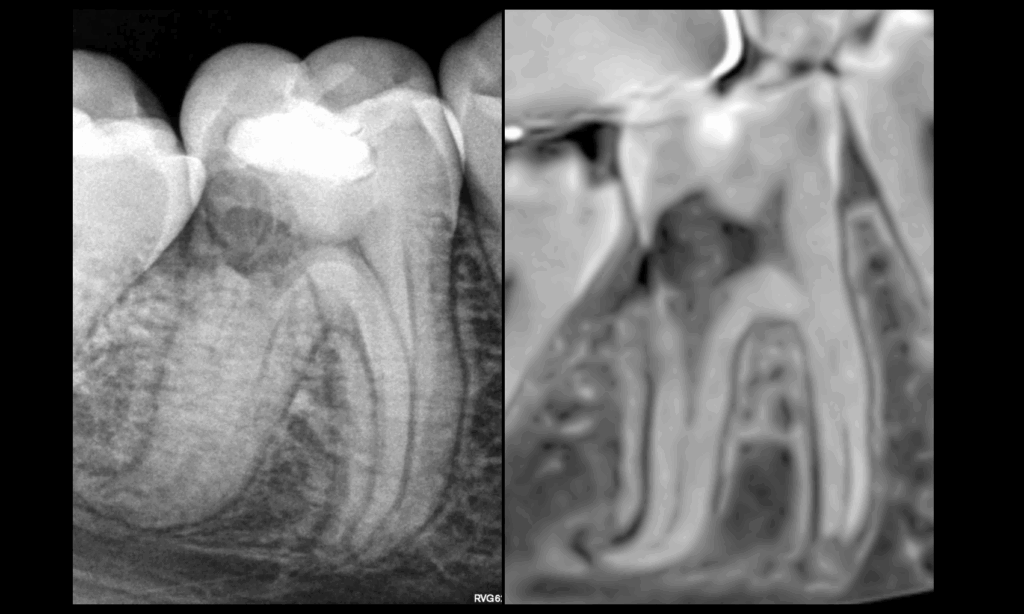

🔍 Résorption radiculaire externe inflammatoire cervicale distale

❓ 𝐐𝐮𝐞𝐥 𝐞𝐬𝐭 𝐥𝐞 𝐩𝐥𝐮𝐬 𝐠𝐫𝐨𝐬 𝐩𝐫𝐨𝐛𝐥𝐞̀𝐦𝐞 𝐢𝐜𝐢 ?

➡️ 𝐁𝐢𝐨𝐦𝐞́𝐜𝐚𝐧𝐢𝐪𝐮𝐞 & 𝐩𝐫𝐨𝐭𝐡𝐞́𝐭𝐢𝐪𝐮𝐞

📌 𝐓𝐞𝐜𝐡𝐧𝐢𝐪𝐮𝐞𝐦𝐞𝐧𝐭, 𝐥𝐞 𝐭𝐫𝐚𝐢𝐭𝐞𝐦𝐞𝐧𝐭 𝐜𝐚𝐧𝐚𝐥𝐚𝐢𝐫𝐞 𝐞𝐬𝐭 𝐫𝐞́𝐚𝐥𝐢𝐬𝐚𝐛𝐥𝐞.

❗❓ 𝐋𝐞 𝐩𝐫𝐨𝐛𝐥𝐞̀𝐦𝐞 𝐚𝐩𝐫𝐞̀𝐬 𝐜𝐮𝐫𝐞𝐭𝐚𝐠𝐞 :

- Fragilisation biomécanique de la dent

- Possibilité de reconstruction fiable et pérenne dans le temps

➡️ 𝐈𝐧𝐝𝐢𝐜𝐚𝐭𝐢𝐨𝐧 𝐝’𝐚𝐯𝐮𝐥𝐬𝐢𝐨𝐧